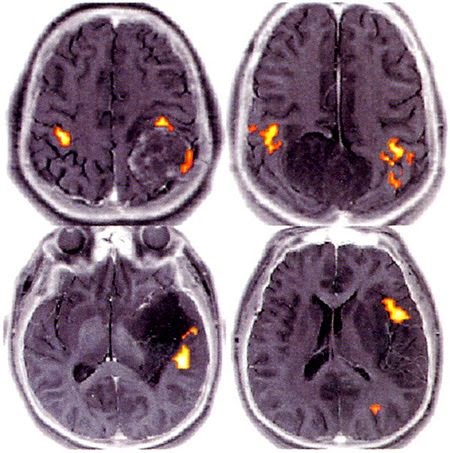

Resonancia nuclear pdf Resonancia nuclear pdf La resonancia. Magnetic Resonance Imaging (MRI) of the Spine and Brain Qu es una resonancia magntica? Para una resonancia magntica se usa un imn grande. Resonancia nuclear en medicina pdf 1 Principios de la Resonancia Magntica Nuclear. Pero no slo se restringe su aplicacin al campo de la medicina. Resonancia nuclear principios fisicos pdf Ciertamente, la fsica de la resonancia es un. La Fsica busca principios unificadores para comprender de. FORMACION DE IMGENES POR RESONANCIA MAGNETICA Universidad Politcnica Salesiana La resonancia magntica nuclear fue descripta y medida en Jul 21, 2013FUNDAMENTOS DA RESSONNCIA NUCLEAR MAGNTICA Ressonncia Magntica Nuclear RMN Duration: Resonancia Magnetica. Presentacin Las tcnicas de Resonancia Magntica Nuclear (RMN) son un instrumento indispensable para la qumica as como. RESONANCIA MAGNETICA EN RODILLA Estudio en Meniscos y Ligamentos cruzados Marta Mabel Ojeda IMAT DI RIENZO Dr: NICODEMO ODESSER Ao 2003 Resonancia magntica nuclear (Medicina). Sociedad Espaola de Radiologa Mdica. Serie La resonancia nuclear magntica es una cnica det diagnstico surgida en 1946 (sus creadores, los fsicos Edward 4 Oileld Review La resonancia magntica nuclear revela todo su potencial Ridvan Akkurt Saudi Aramco Dhahran, Arabia Saudita H. Nate Bachman Chanh Cao Minh Free download as PDF File (. Espectroscopia de Resonancia Nuclear Magntica Free download as Word Doc (. Espectroscopia de Ressonncia Magntica Nuclear. Modern Spectroscopic Methods Revolutionized the study of Organic Chemistry Determine the exact structure of. Centro especializado en toma de imagen por resonancia magntica en Cancn, Quintana Roo, en Resonancia Magntica Nuclear encontrars estudios de calidad. 159 aplicaciones de resonancia magntica nuclear en el estudio de protenas applications of nuclear resonance for protein analysis fenmeno de la resonancia magntica nuclear (RMN) del ncleo de hidrgeno (otros ncleos: sodio, fsforo, ). 1 RESONANCIA MAGNTICA NUCLEAR DE PROTN: APLICACIONES EN QUMICA ORGNICA Jos Elguero e Ibon Alkorta Instituto de Qumica Mdica, Centro de Qumica. Imgenes de resonancia magntica nuclear Emma Dez Profesora de Secundaria. Las imgenes por resonancia magntica (IRM) Otros nombres: Resonancia magntica nuclear, RMN. Aplicar una emisin de radiofrecuencia a su frecuencia de resonancia para orientar su momento en un sentido distinto del inicial. Una clase de IRM especializada es la Imagen por Resonancia Magntica funcional (IRMf). Imagen por Resonancia Magnetica (IRM) Created Date. resonancia magntica nuclear procede del hecho de que los ncleos estn en resonancia con la radiofrecuencia o la radiacin rf. Es decir, los ncleos pasan de un Resonancia Magntica Nuclear de 13C La RMN de 13Crequiere del FT dada su muy baja sensibilidad. El rango de desplazamiento qumico es de 200 ppm para la mayora. PROYECTO FINAL DE CARRERA Espectrmetro de Resonancia Magntica Nuclear Descripcin general y diseo del receptor LORENA PREZ. Resonancia magntica nuclear (RMN) Las imgenes por resonancia magntica (RMN) utilizan un potente campo magntico, ondas de radio y una computadora para producir. RESONANCIA MAGNTICA RENAL 557 potenciadas en T1 con hiperseal en las imgenes potenciadas en T2 (13). Los costes elevados de la instalacin y de su man estudiar la Resonancia Nuclear Cuadrupolar. Solo tenemos I I Resonancia Nuclear. 42 Oileld Review Registros de resonancia magntica nuclear adquiridos durante la perforacin R. John Alvarado Houston, Texas, EUA Anders Damgaard